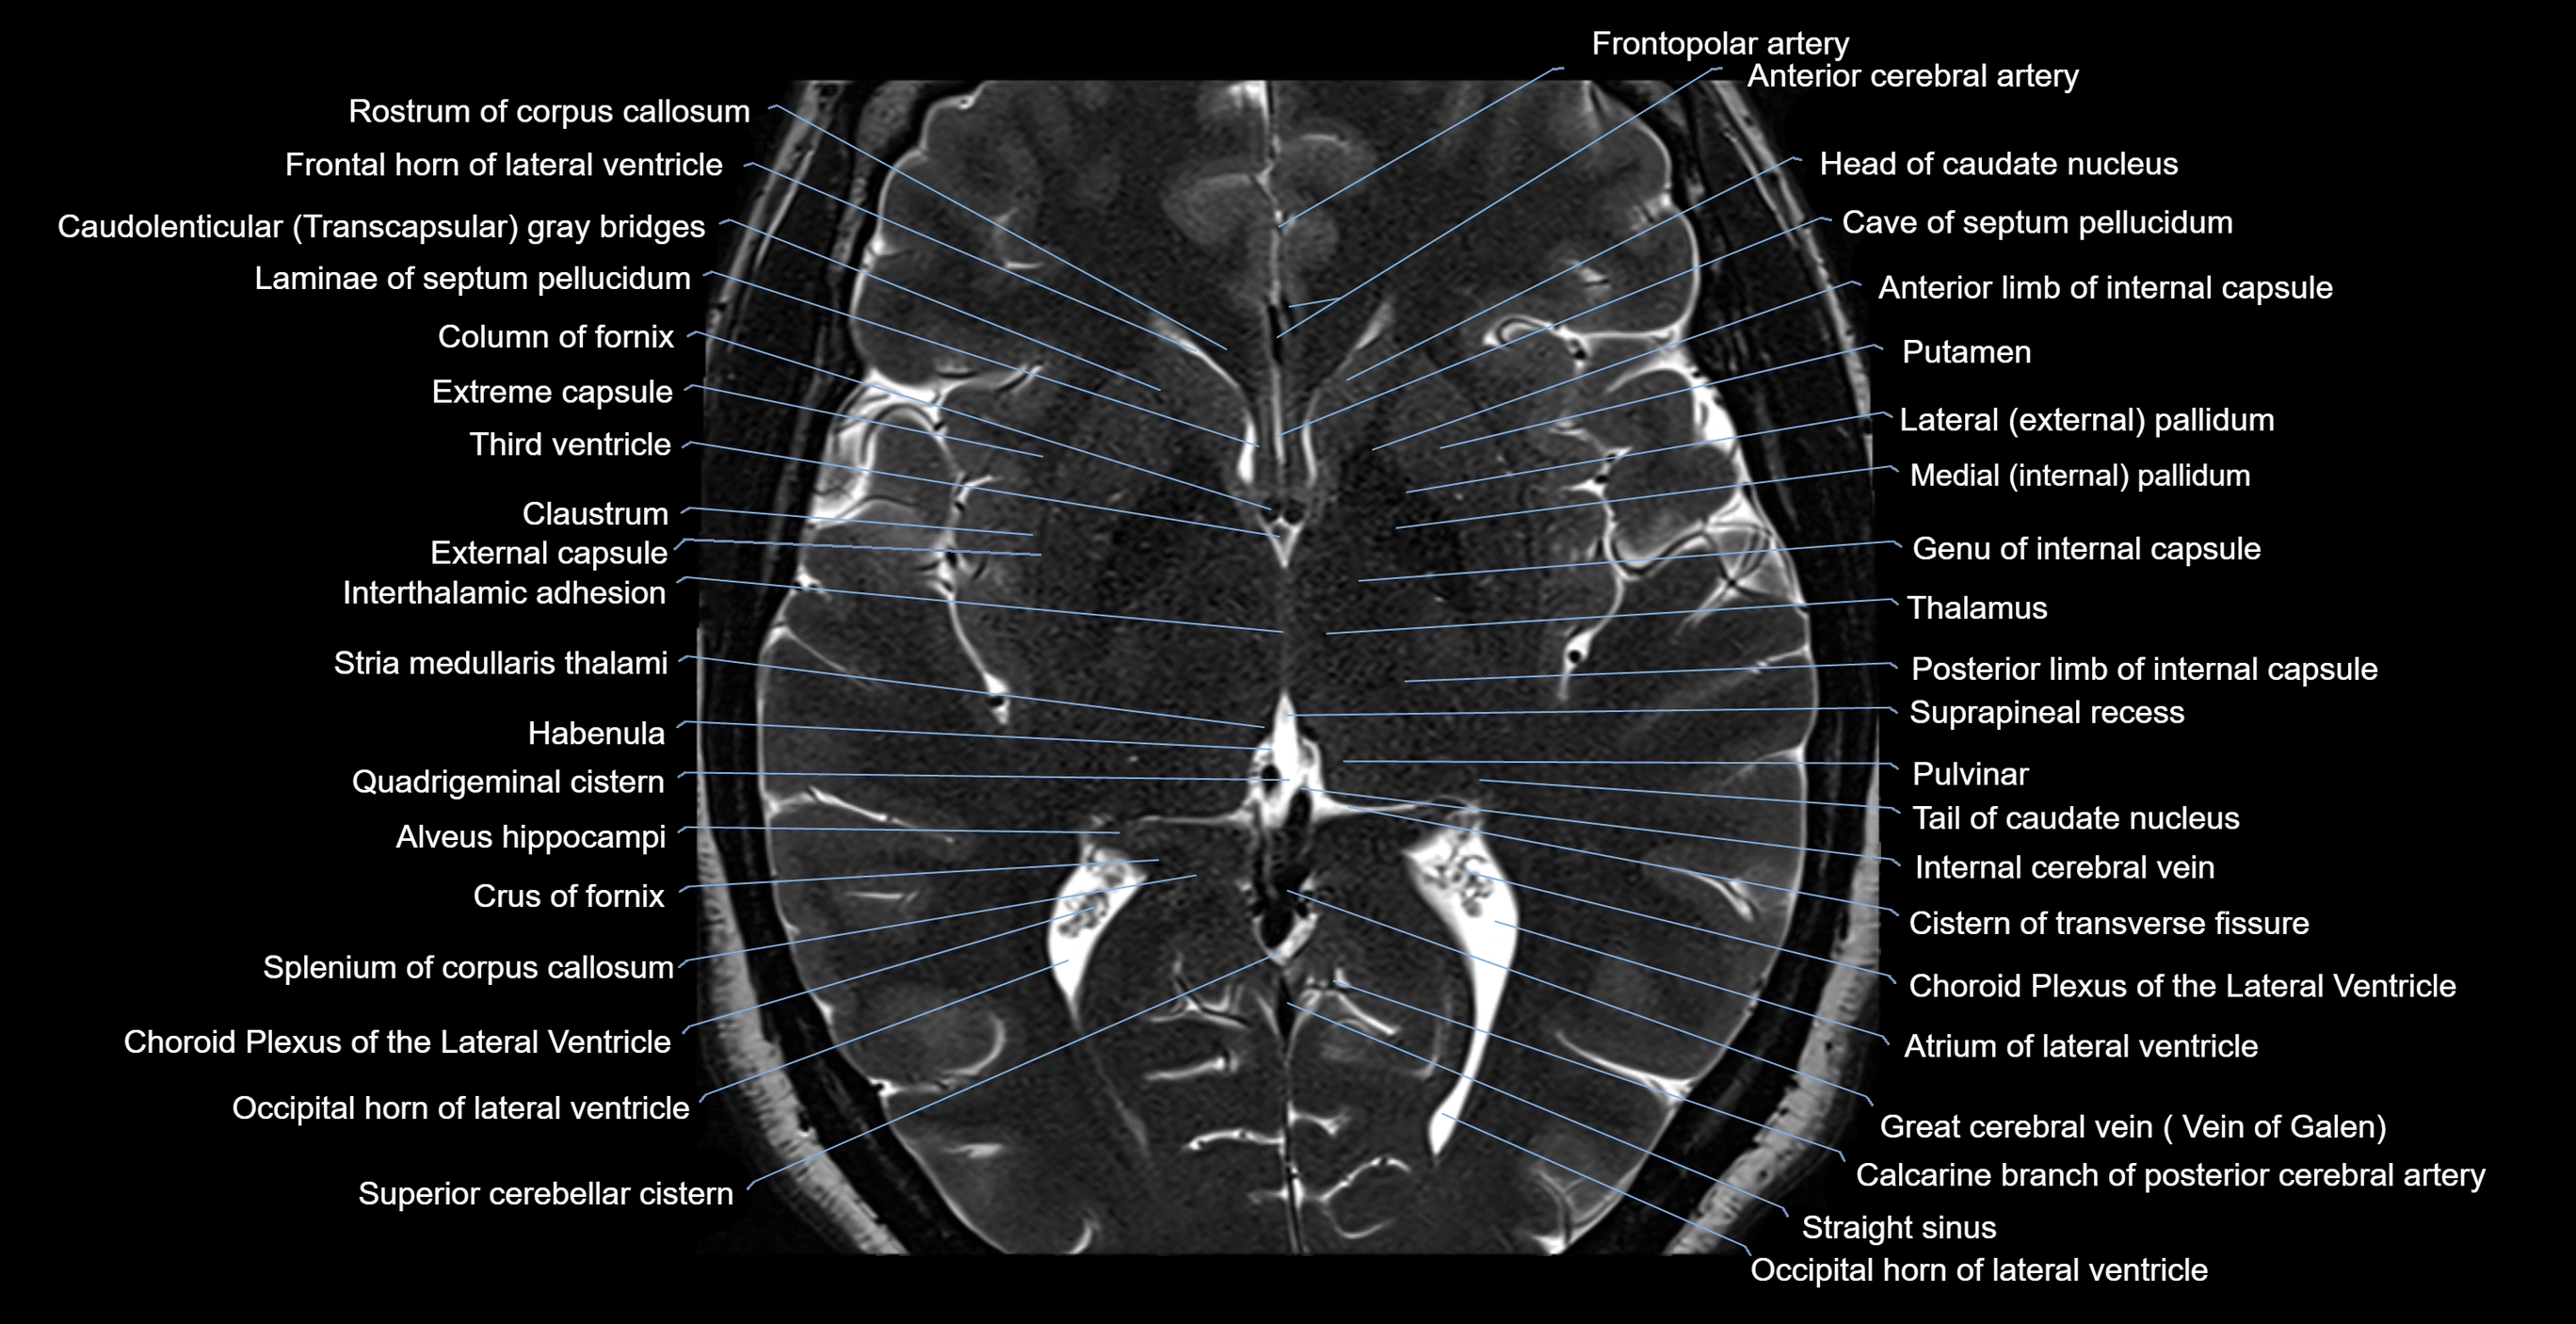

MRI images